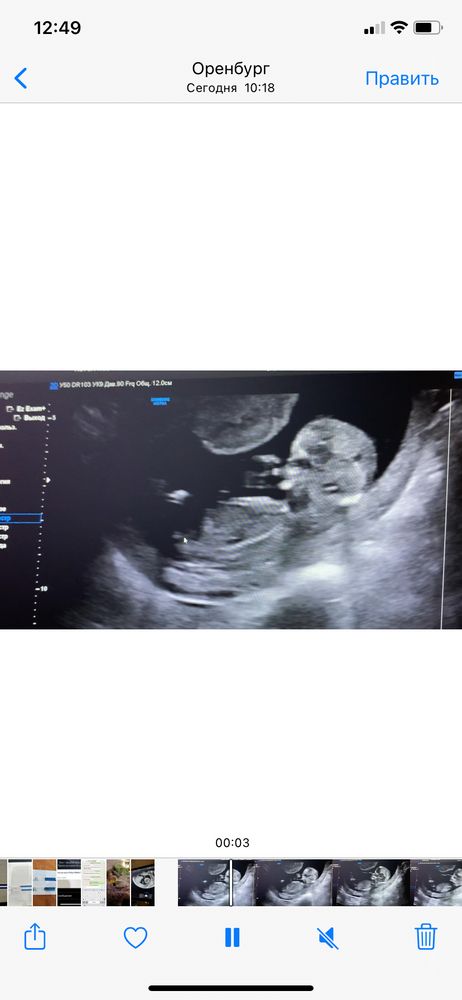

фото сбоку и сидя на попке